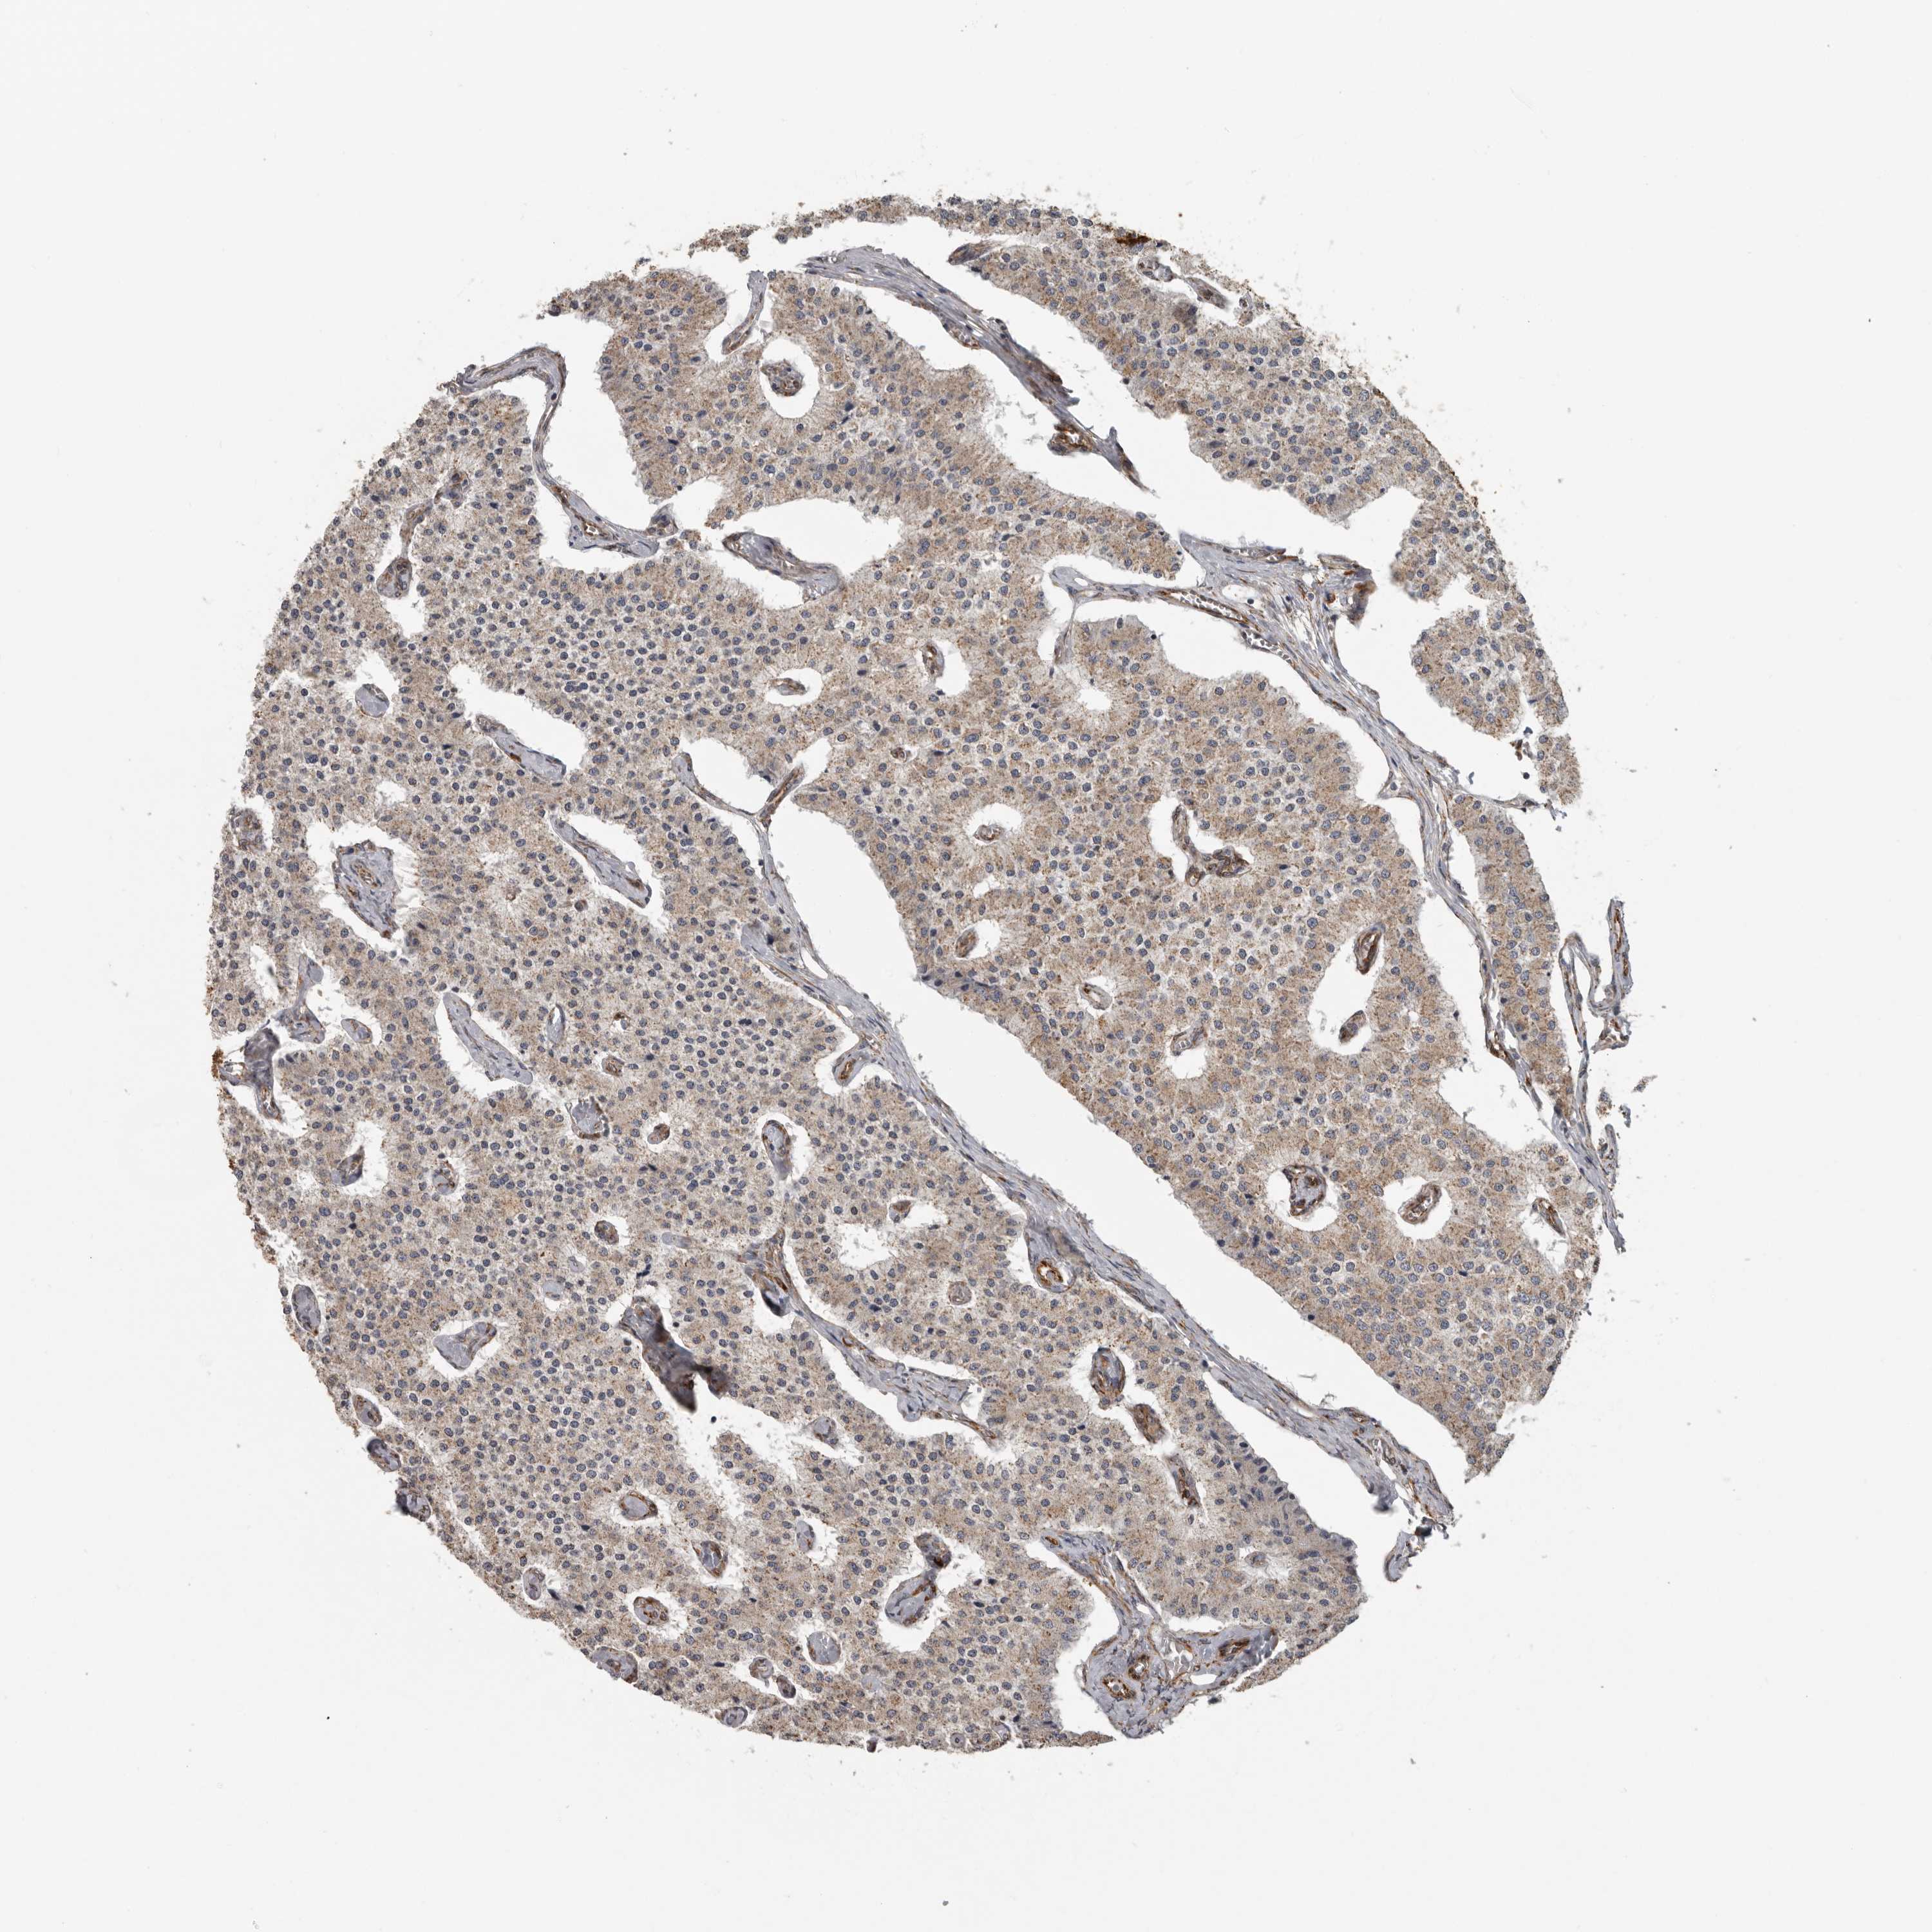

CARCINOID - Protein expressioni

A mouse-over function shows sample information and annotation data. Click on an image to view it in a full screen mode. Samples can be filtered based on level of antibody staining by selecting one or several of the following categories: high, medium, low and not detected. The assay and annotation is described here.

Antibody stainingi

Antibody staining in the annotated cell types in the current human tissue is reported as not detected, low, medium, or high, based on conventional immunohistochemistry profiling in selected tissues. This score is based on the combination of the staining intensity and fraction of stained cells.

Each image is clickable and will lead to virtual microscopy that enables deeper exploration of all samples and also displays staining intensity scores, fraction scores and subcellular localization as well as patient and tissue information for each sample.

Antibody HPA028355

Antibody HPA028357

Staining

High

Medium

Low

Not detected

Intensity

Strong

Moderate

Weak

Negative

Quantity

>75%

75%-25%

<25%

None

Location

Nuclear

Cytoplasmic/membranous

Cytoplasmic/membranous,nuclear

Carcinoid, malignant, NOS

Carcinoma, NOS